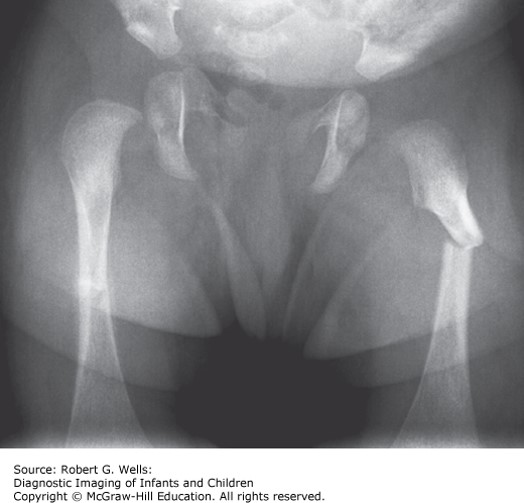

A 14-month-old boy presents with refusal to bear weight on his right leg after falling off the bed.

A 14-month-old boy presents with refusal to bear weight on his right leg after falling off the bed. X-rays demonstrate a midshaft femur fracture. Medical records demonstrate prior visits for a wrist fracture and a tibial fracture over the past 3 months. Physical examination reveals multiple bruises. Skeletal survey demonstrates healing right distal radius and right spiral tibial fractures, but no other healing or new fractures. Head magnetic resonance imaging (MRI) does not reveal any intracranial injury and there are no retinal hemorrhages.

The correct answer is “D.” Concerns regarding osteogenesis imperfecta are frequently entertained in cases of unusual or frequent fractures and may be mistaken for nonaccidental trauma. Numerous genetic causes have been identified, most commonly in the formation of bone involving collagen (COL1A1, COL1A2, and others). Vitamin D levels are normal. Inheritance patterns of the genetic abnormalities include autosomal dominant, recessive, and X-linked forms, but current classification remains based on phenotype. Type I, or nondeforming, is the mildest, and patients typically achieve normal height. Type II is lethal in the perinatal period. Type III often presents at birth with frequent fractures and results in progressive deformity, and type IV is the moderate form. Type V involves ossification of the interosseous membrane, hypertrophic callus formation, or both. Blue sclera are common in types I and III, but individuals with type IV often have white sclera. Patients often have triangular facies and macrocephaly, and may have hearing loss. Short stature, easy bruising, and joint hypermobility may also occur. X-rays often demonstrate osteopenia or wormian bones of the skull.